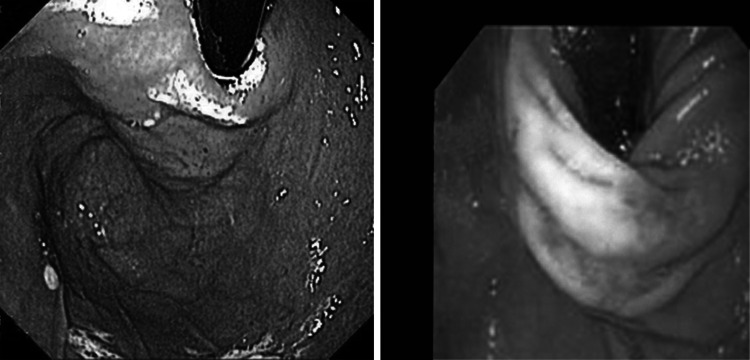

Demographic data for the treated patients are provided in Table 2. The fundus was stapled to the esophagus with two quintuplets in four patients and with three quintuplets in nine patients. On gastroscopic examination immediately after the procedure, the result was anatomically identical to a Dor–Thal anterior fundoplication (see Fig. 2).

Fig. 2.

Retrograde view of trans-oral stapled anterior fundoplication (left) and laparoscopic fundoplication (right). Photograph on right courtesy of Prof. D. Watson, Adelaide, Australia